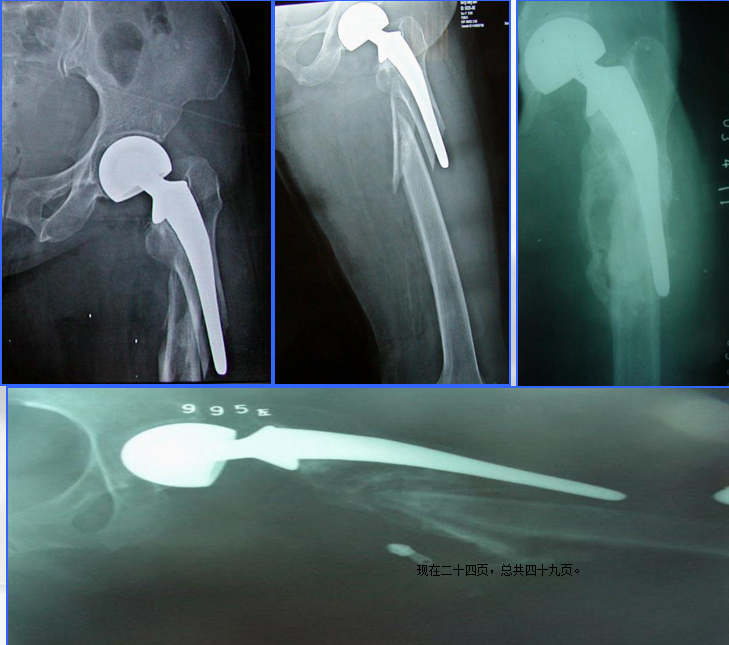

髓内固定:(二)翻修术

①适应征:假体松动的骨折

长柄远端固定非骨水泥型

假体的长度至少要超过骨折端两倍于股骨直径的距离

④对于骨量丢失严重、无法重建的病人:

异体骨假体复合物:适用于年轻的病人,此法可保留软组织和肌肉止点

肿瘤型假体:适用于老年病人,使病人早期负重活动